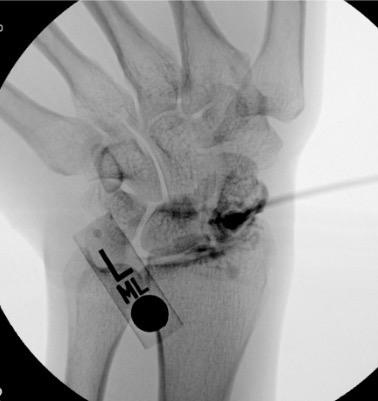

Wrist

Dorsal radiocarpal

Scapholunate interval or radioscaphoid joint; 3–4 cm distal to Lister's tubercle

3–4 mL

Wrist injected volume is small. The radiocarpal compartment holds only 3–4 mL — resistance is felt quickly. Stop injecting if resistance increases before target volume; overdistension causes capsular rupture and contrast extravasation that can obscure compartment communication findings.

Finding

Fluoroscopic Appearance

TFCC tear

Contrast from radiocarpal joint fills the distal radioulnar joint (DRUJ)

Scapholunate ligament tear

Contrast from radiocarpal joint fills the midcarpal compartment through the scapholunate interval

Lunotriquetral ligament tear

Contrast fills midcarpal from radiocarpal through lunotriquetral interval

Wrist: wrong compartment

Wrist has three compartments (radiocarpal, midcarpal, DRUJ) — each must be entered separately for complete three-compartment arthrogram if indicated; inadvertent midcarpal entry misses radiocarpal pathology